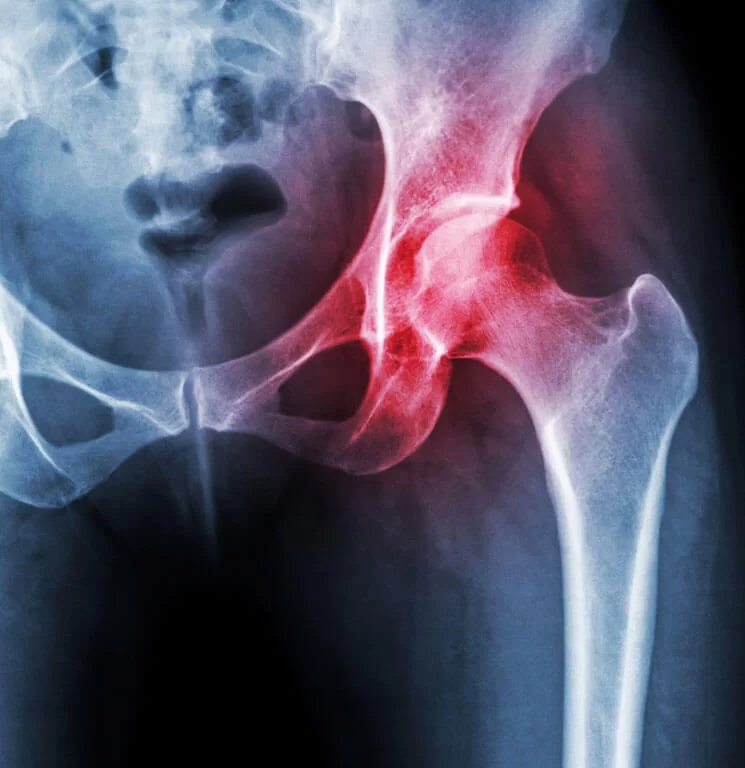

Diseased hip: osteoarthritis causes the articular cartilage to wear away, exposing bone and resulting in pain in the groin, hip, buttock or knee with restricted movement. Other inflammatory conditions like rheumatoid arthritis can also damage the hip.

Indications

• X‑ray changes of degenerative joint disease